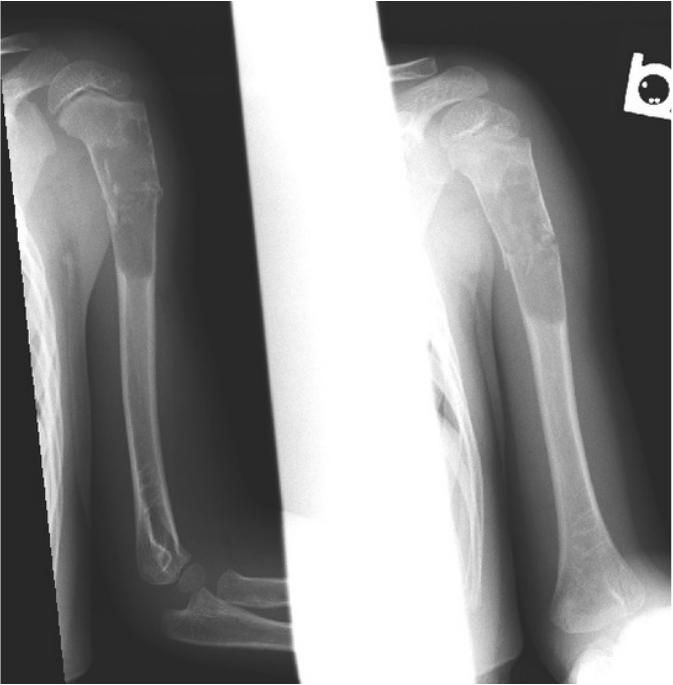

Same patient several weeks later showing callus from fracture healing:

Simple bone cysts, aka unicameral bone cysts, are a fluid-filled cavity within the bone and are most commonly found in the immature skeleton. The etiology is unknown, although it has been speculated they arise from growth disturbance to synovial tissue around a joint or venous congestion. They are benign and usually painless, although they can weaken the bone which predisposes to fracture. SBC's are most commonly found in long tubular bones however others like the talus, calcaneus, and ilium have been described. X-ray findings are a characteristic well defined, mildly expansile lesion with a sclerotic margin, intact cortex, and no soft tissue mass. There is no periosteal reaction unless a healing fracture is present. If radiographs are equivocal then MRI may be performed for confirmation.

Incidentally found lesions are usually left to observation with modification of activities to reduce the risk to fracture. Cysts commonly can enlarge during times of bone growth and heal as the patient reaches skeletal maturity. As stated above, approximately 25% of cysts will spontaneously heal if a pathologic fracture has occurred. Aspiration and injection of corticosteroid into the cyst or curettage with bone graft are surgical options in cases of high risk of fracture. The cyst, however, recurs in 25-50% of patients regardless of the treatment.